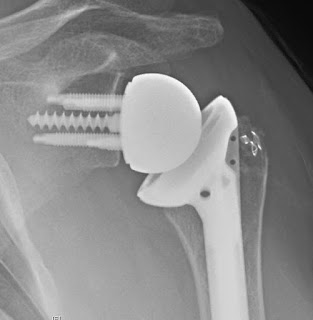

A woman in her late 50s had shoulder pain and weakness of her left shoulder after a failed cuff repair.

She desired a reverse total shoulder. At surgery there was an intact subscapularis but absent supraspinatus and infraspinatus.

Her sequential Grashey views are shown here

1.4 months post op

3 months post op5.9 months post op. At this time she complained of some left shoulder pain after lifting her grandchild.

7.4 months post op. The left shoulder pain remained.

Comment: The post operative views suggest incomplete seating of the base plate, which may have subjected the screws to bending forces leading to their failure from fatigue.